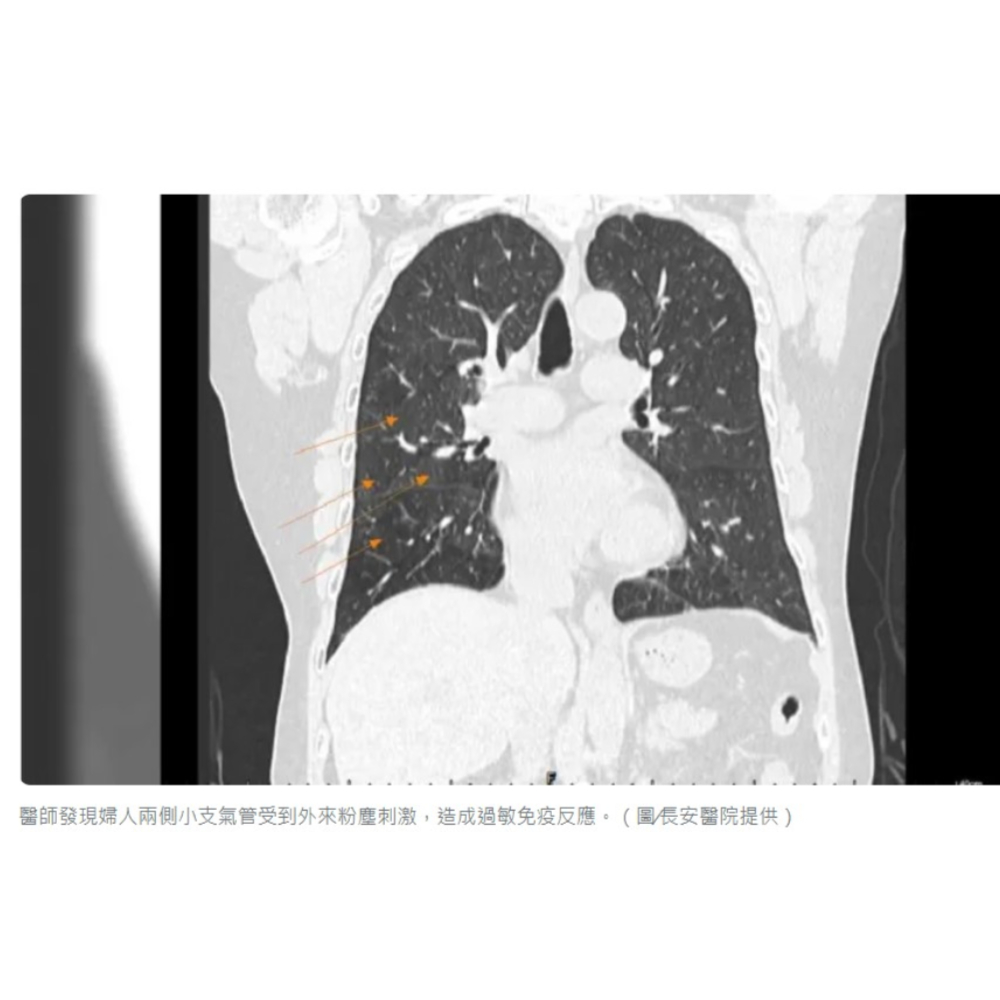

The woman, suffering from chronic asthma, chronic cough, and chest tightness for years, underwent medical examination. Initial chest X-rays showed minor infiltration and swelling. However, a computed tomography (CT) scan revealed distinctive patchy changes on both sides of the lungs, resembling a quilt pattern. Dr. Hsu Jen-wen, a pulmonologist at Chang An Hospital, explained that these changes indicate irritation of the small bronchi on both sides due to external dust exposure, triggering an allergic immune response and causing persistent inflammation in the lungs.